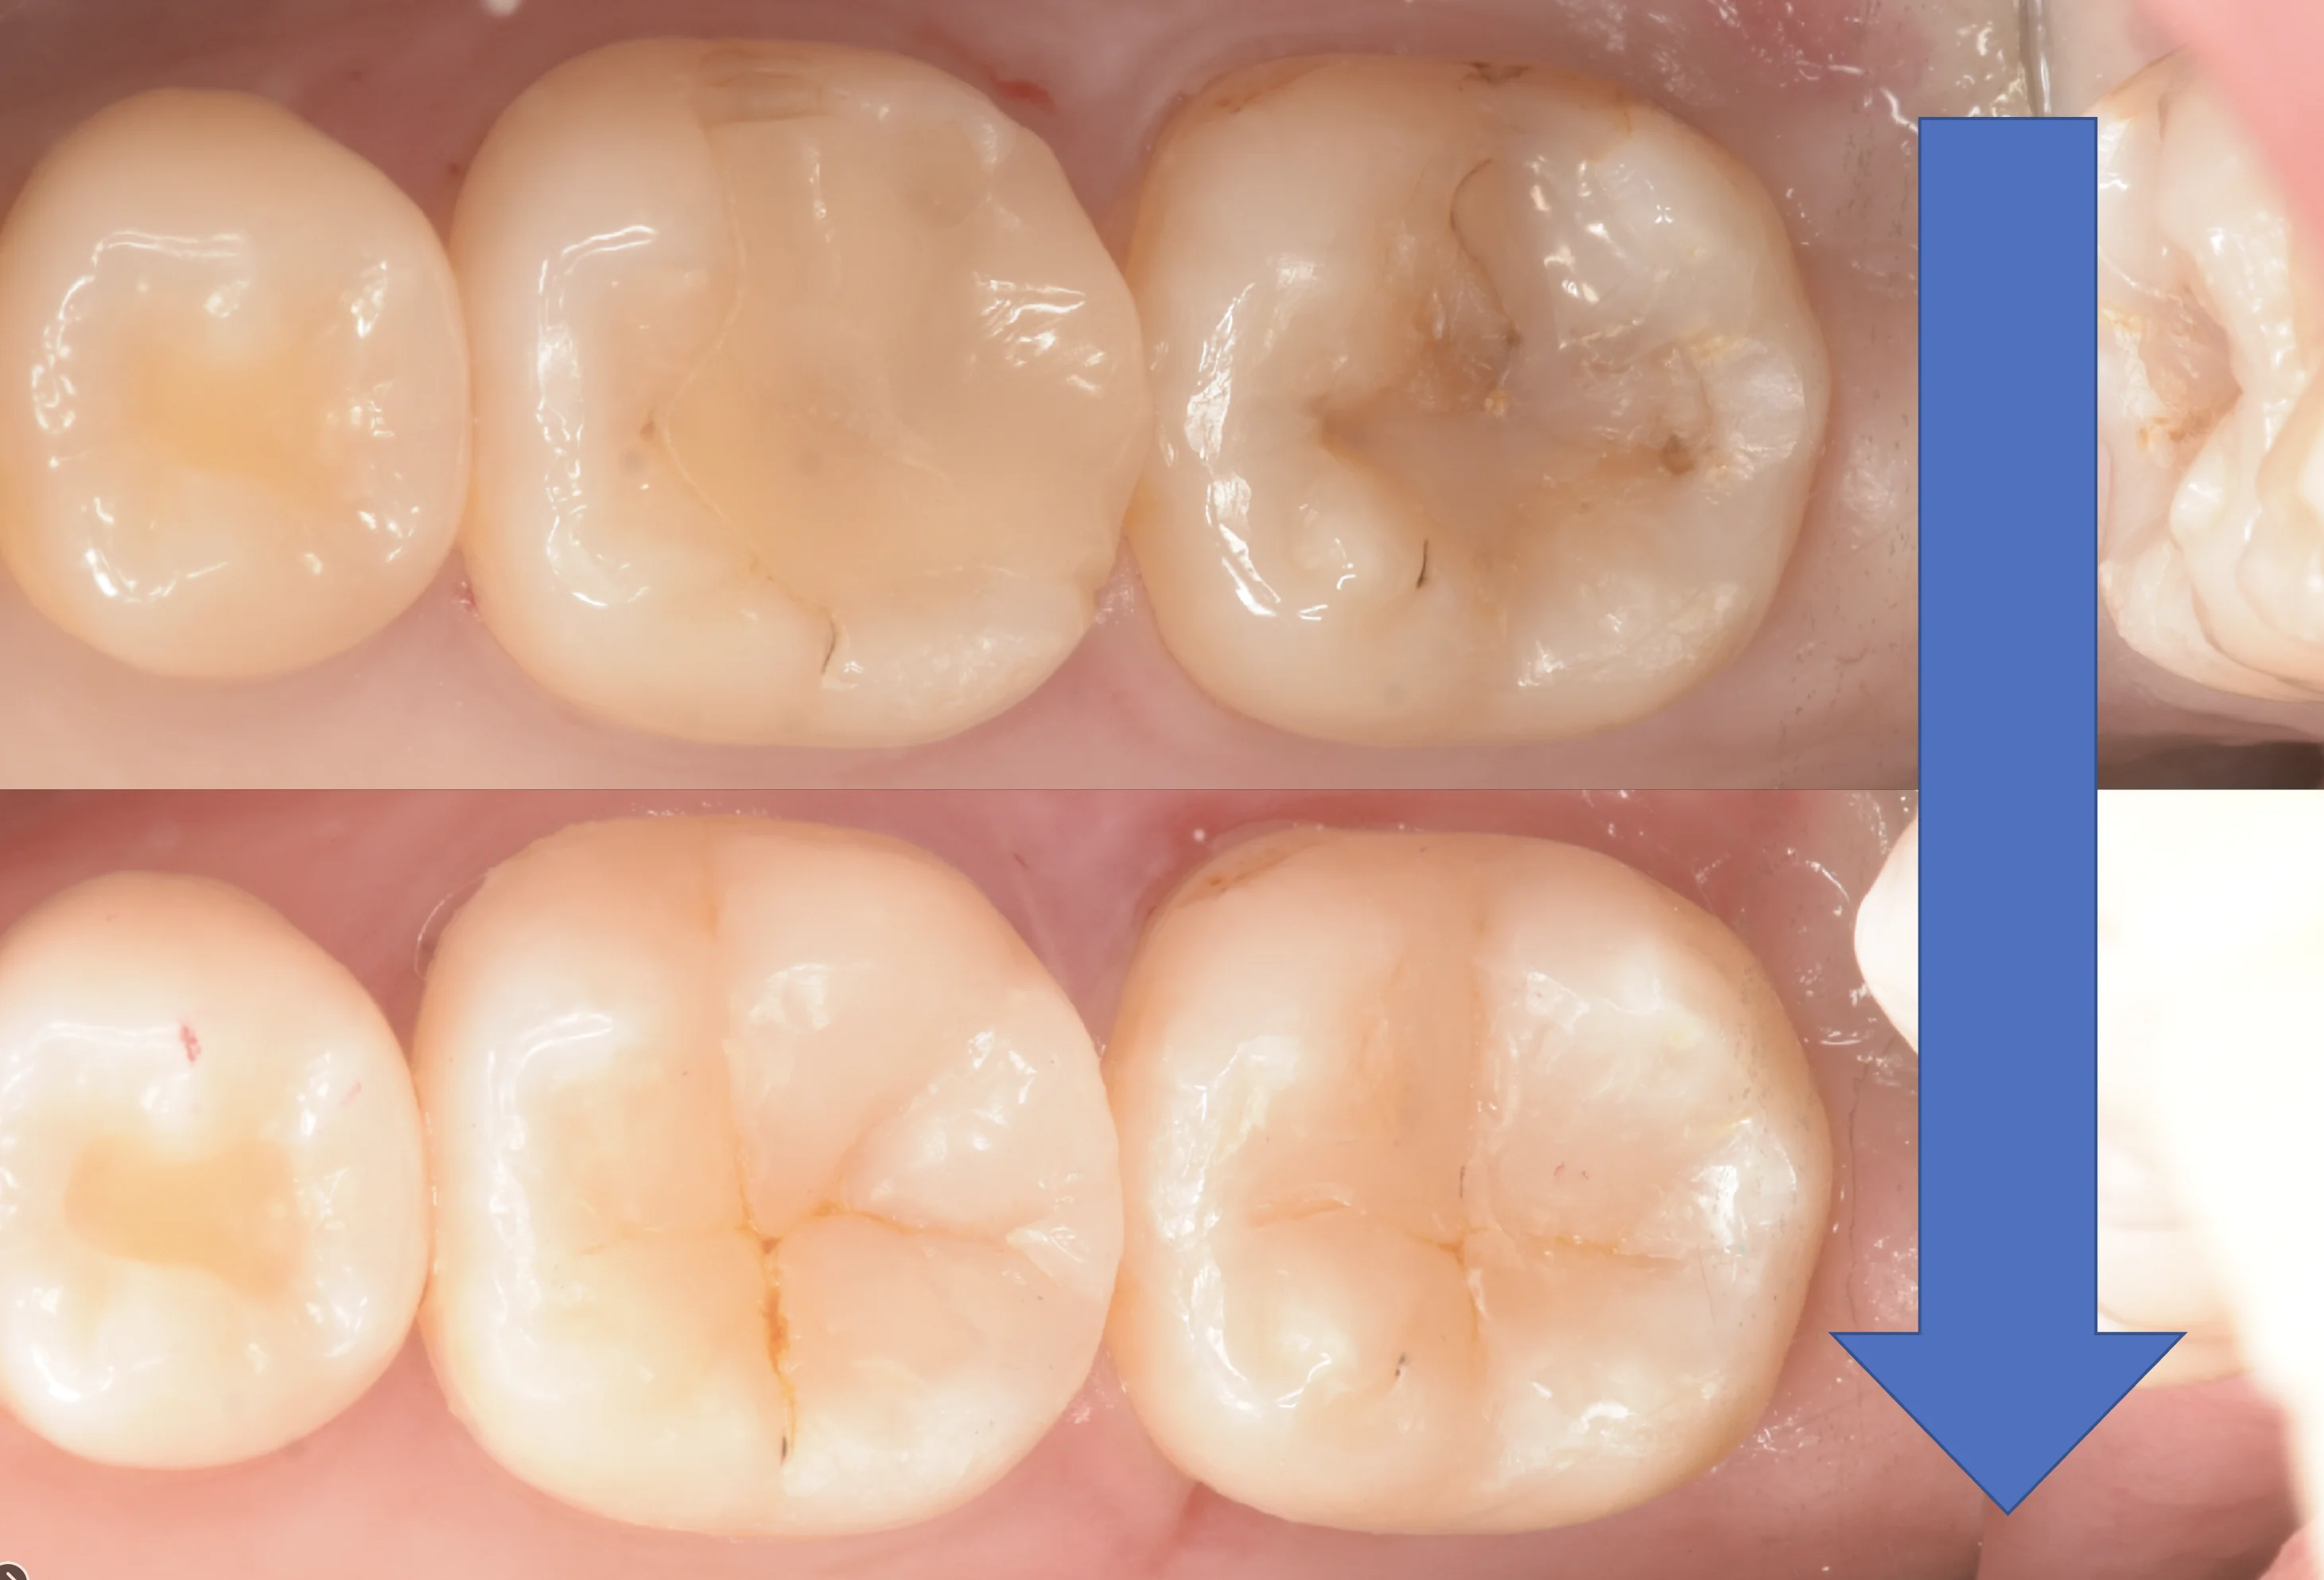

術前術後の写真がこちらです。

歯科医師の方のCAD/CAMインレーを治療。|坂寄歯科医院(取手市藤代) - 画像9

術前術後